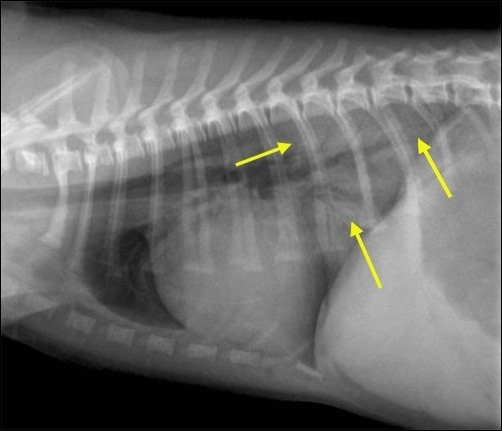

При всех формах отека легких главным диагностическим тестом является грудная рентгенограмма. Грудная рентгенограмма подтверждает или опровергает наличие жидкости в легких (затемнение легочных полей с одной или обеих сторон), при сердечной патологии – увеличение в размерах тени сердца. Распределение инфильтратов может помочь в определении этиологии. В человеческой медицине давление заклинивания в лёгочных капиллярах (ДЗЛК) является золотым стандартом для дифференцировки кардиогенного от некардиогенного отека легких, но в ветеринарии применяется очень редко, так как для его измерения необходимо установить катетер в легочную артерию.

рис. 1 — отек

рис. 2 — норма

У собак с кардиогенным отеком грудная рентгенограмма документирует кардиомегалию, венозный застой, интерстициальную и альвеолярную инфильтрацию. У собак инфильтрация обычно начинается в перихилярной области (корень легкого), но может расширяться и в тяжелых случаях поражать всю паренхиму легкого. У кошек с кардиогенным отеком на рентгене так же можно увидеть кардиомегалию, застой в легочных венах, но картина отека вариабельна.Также желательно проводить следующие исследования: эхокардиография, ЭКГ, измерение ДЗЛК.

У животных с некардиогенным отеком грудная рентгенограмма покажет инфильтрацию паренхимы легких без кардиомегалии. Другие диагностические тесты: нормальная эхокардиограмма и нормальное ДЗЛК.